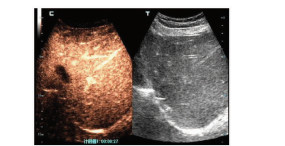

A case of severe allergic hepatitis caused by eosinophilia

Jie SU, Jingyu WANG, Xing HUANG, Yu PAN, Yue QI, Rui HUA

2022, 38(1): 164-166. DOI: 10.3969/j.issn.1001-5256.2022.01.026

Abstract(1585) HTML (308) PDF (2349KB)(97)

Abstract: